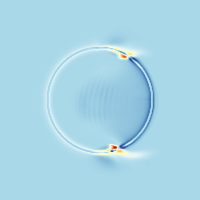

Normalisation of medical images is a important step for data acquisition

Before

linear registration :

After

Non Linear registration

Diffeomorphic matching => Keeps the Topology